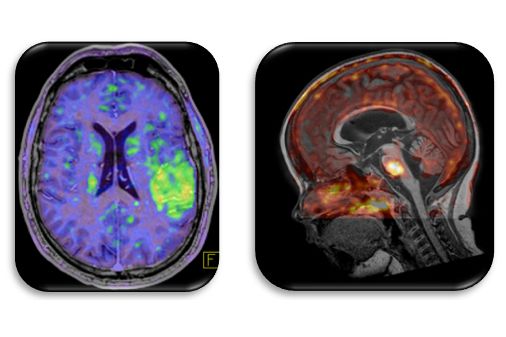

Innovative Training Network ITN is a special funding programme to fund networks that train young researchers. The Training Network "HYBRID" (Healthcare Yearns for Bright Researchers for Imaging Data, MSCA-ITN-ETN 764458), focuses on hybrid molecular imaging and PET/MRI in particular. The programme consists of three work packages: multi-centre data collection, multi-parametric data processing and clinical translation of new diagnostic approaches. Under this programme, standardised quantitative evaluation procedures for multi-parametric imaging will be developed over the next four years and – in combination with additional biomarker information (e.g. histology, liquid biopsy) – will go beyond purely visual assessment of image data. This project is particularly characterised by the multi-centre approach and the preferred use of integrated, hybrid imaging techniques. Ultimately, it is hoped that the findings from the various research areas will lead to improved diagnostic techniques (including predictive models; keyword "RadiomicsPlus") and new approaches for image-based treatments.